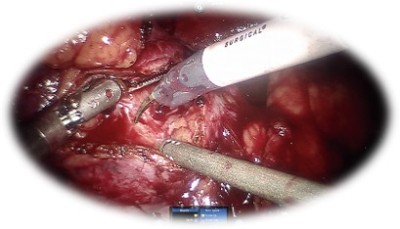

Prostatectomia radicală robotică:

• Standardul de aur în tratamentul chirurgical al cancerului prostatic localizat

• Presupune îndepărtarea glandei prostatice împreună cu veziculele seminale și ganglionilor regionali

• Oferă:

• Rata complicațiilor intra și postoperatorie redusă, cu sângerare minimă

• Recuperare rapidă cu spitalizare redusă

• Calitate foarte bună a vieții